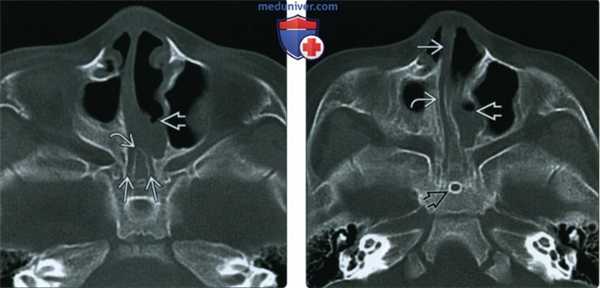

(Слева) При аксиальной КТ в костном окне у новорожденного с комплексной аномалией носа определяется двухсторонняя атрезия хоан, аплазия полости носа справа, утолщение сошника, визуализируется слой жидкости в полости носа слева.

(Справа) При аксиальной КТ в костном окне у этого же ребенка визуализируется слой жидкости в полости носа слева, спереди от отсутствующего хоанального отверстия. Обратите внимание на отсутствие полости носа справа и смещение перегородки к латеральной стенке носовой полости. Визуализируется персистирующий краниофарингеальный канал (случайная находка).